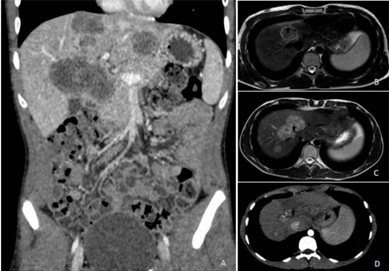

Paciente de 45 anos, sexo masculino, conta história de dificuldade de evacuar completamente e necessidade de tentar evacuar quatro a cinco vezes ao dia, em pequena quantidade, sem sangue, muco ou alteração no formato das fezes, há cerca de um mês e meio. Há 10 dias, iniciou dor abdominal difusa em cólica e alguns episódios de vômitos. Perdeu 5 kg no último mês. Refere ser constipado de longa data. Nega doenças prévias. É tabagista ativo (40 anos-maço). Exame físico: estado geral preservado, descorado (++/4), anictérico, afebril. Palpação do abdômen: fígado palpável a 14 cm do rebordo costal direito e 9 cm do rebordo costal esquerdo, endurecido e aparentemente irregular; baço não palpável. Exames laboratoriais: hemoglobina 10,1 g/L; TGO 58 UI/L; TGP 52 UI/L; fosfatase alcalina 287 UI/L, gama GT 274 UI/L; bilirrubina: total 1,4 mg/d; indireta 0,5 mg/dL e direta 0,9mg/d, RNI 1,42. Tomografia computadorizada de abdômen com imagem abaixo.

Em relação a esse paciente, a hipótese diagnóstica e a conduta são, respectivamente: